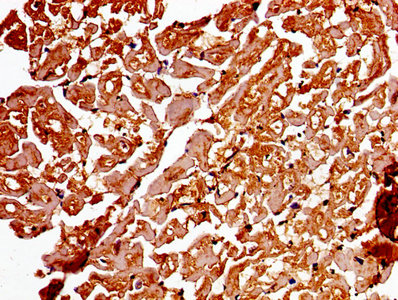

IHC image of CSB-PA001311LA01HU diluted at 1:250 and staining in paraffin-embedded human lung tissue performed on a Leica BondTM system. After dewaxing and hydration, antigen retrieval was mediated by high pressure in a citrate buffer (pH 6.0). Section was blocked with 10% normal goat serum 30min at RT. Then primary antibody (1% BSA) was incubated at 4°C overnight. The primary is detected by a biotinylated secondary antibody and visualized using an HRP conjugated SP system.